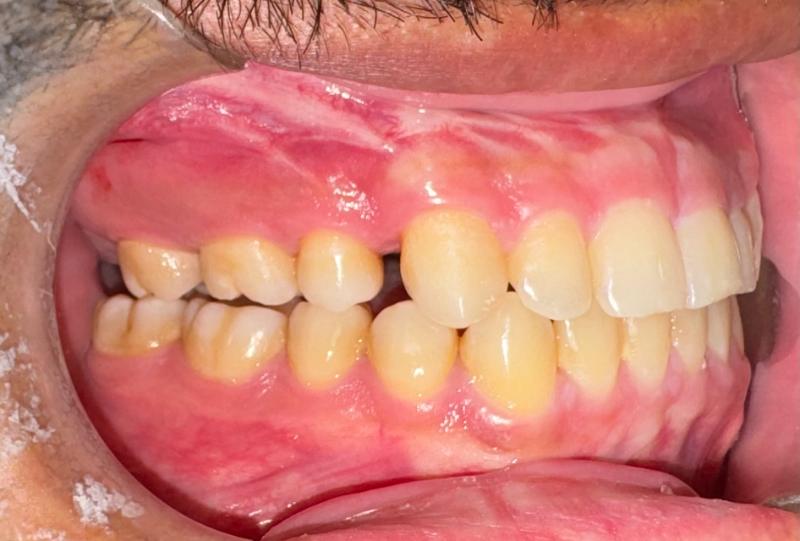

Prima

Il paziente, di 27 anni, si presenta alla mia osservazione già in trattamento ortodontico, a causa di un evidente morso inverso, manifestazione tipica di una terza classe dento-scheletrica.

In collaborazione con il Dott. Laganà e l’ortodontista Di Benedetti, è stato effettuato un attento studio del caso. Si è deciso di completare la fase di decompensazione ortodontica, spiegando al paziente che in questa fase avrebbe assistito ad una temporanea accentuazione del difetto estetico e funzionale, necessaria per garantire il successo della fase chirurgica.